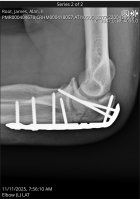

Well, it appears that I have lived - at least to this point. The doc was happy with the procedure, and left me with optimism. The food is good, the girls are pretty, and I've found out who the ice cream guy is.

Amen! I had surgery same day, no where near as extensive 'tho (rotator cuff). Hope your journey back to full health goes smoothly.I wanna thank y'all for your prayers and good wishes, it's working!